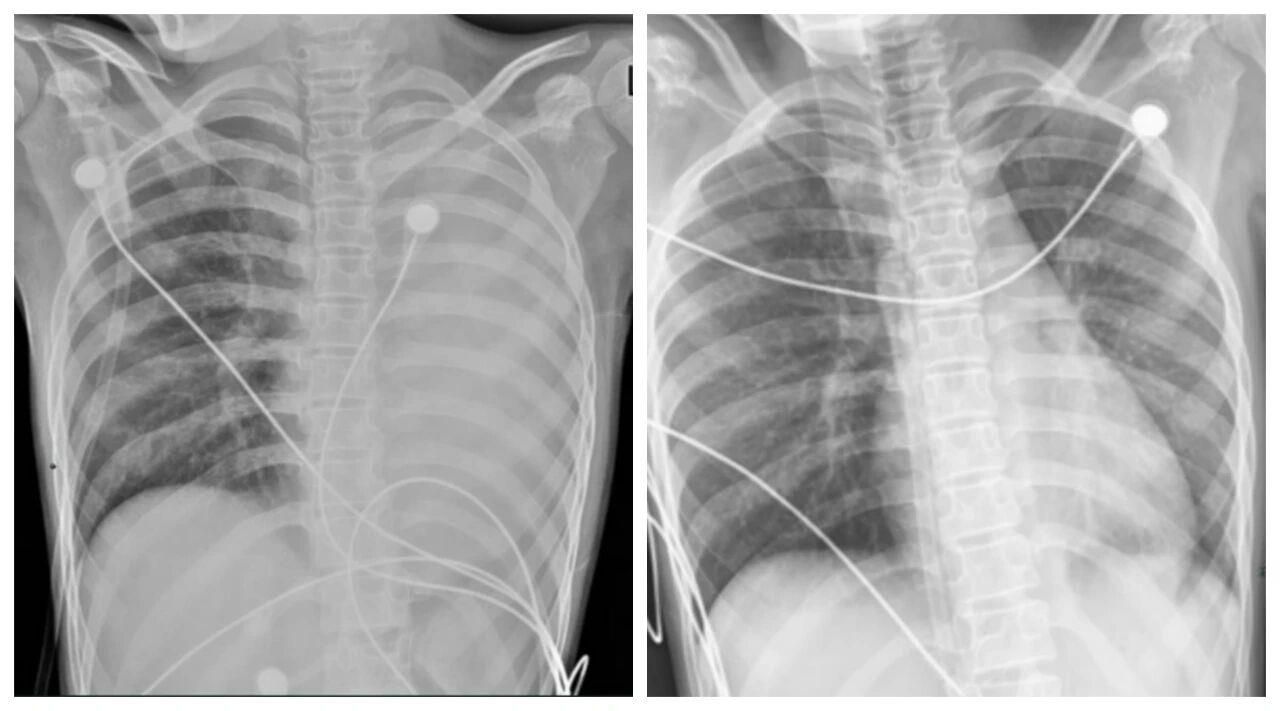

一开始,她只是轻微咳嗽,发热后在外院检查提示肺炎、肺不张,转诊到浙大四院儿科时,笑笑出现呼吸急促、胸闷胸痛,血氧饱和度勉强维持在90%左右,胸片显示左肺已完全呈“白肺”改变,病情急剧恶化。

△笑笑治疗前,左肺呈“白肺”状态,治疗后“白肺”被吸收,心脏边缘清晰可见。图源:浙大四院

术后第二天,笑笑呼吸困难、胸痛的症状明显好转,病情得到了初步控制。经过精准抗感染、祛痰、抗炎等系列治疗,笑笑逐渐康复,顺利出院。